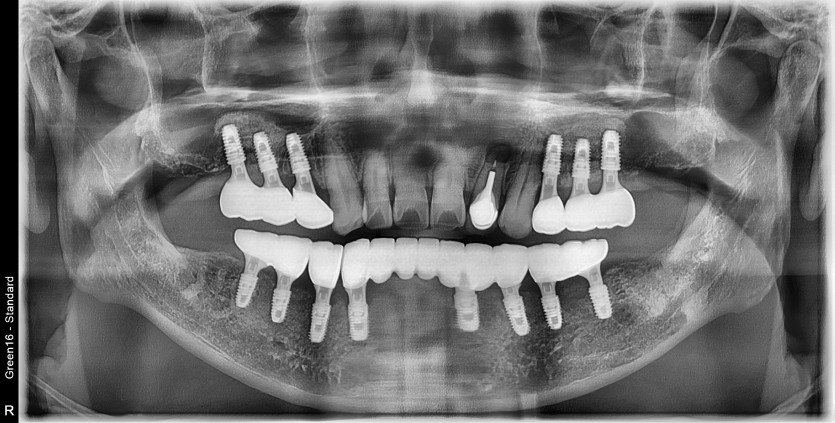

하악 전체 임플란트 증례입니다.(상악 일부)

14개의 임플란트로 완성하였습니다.